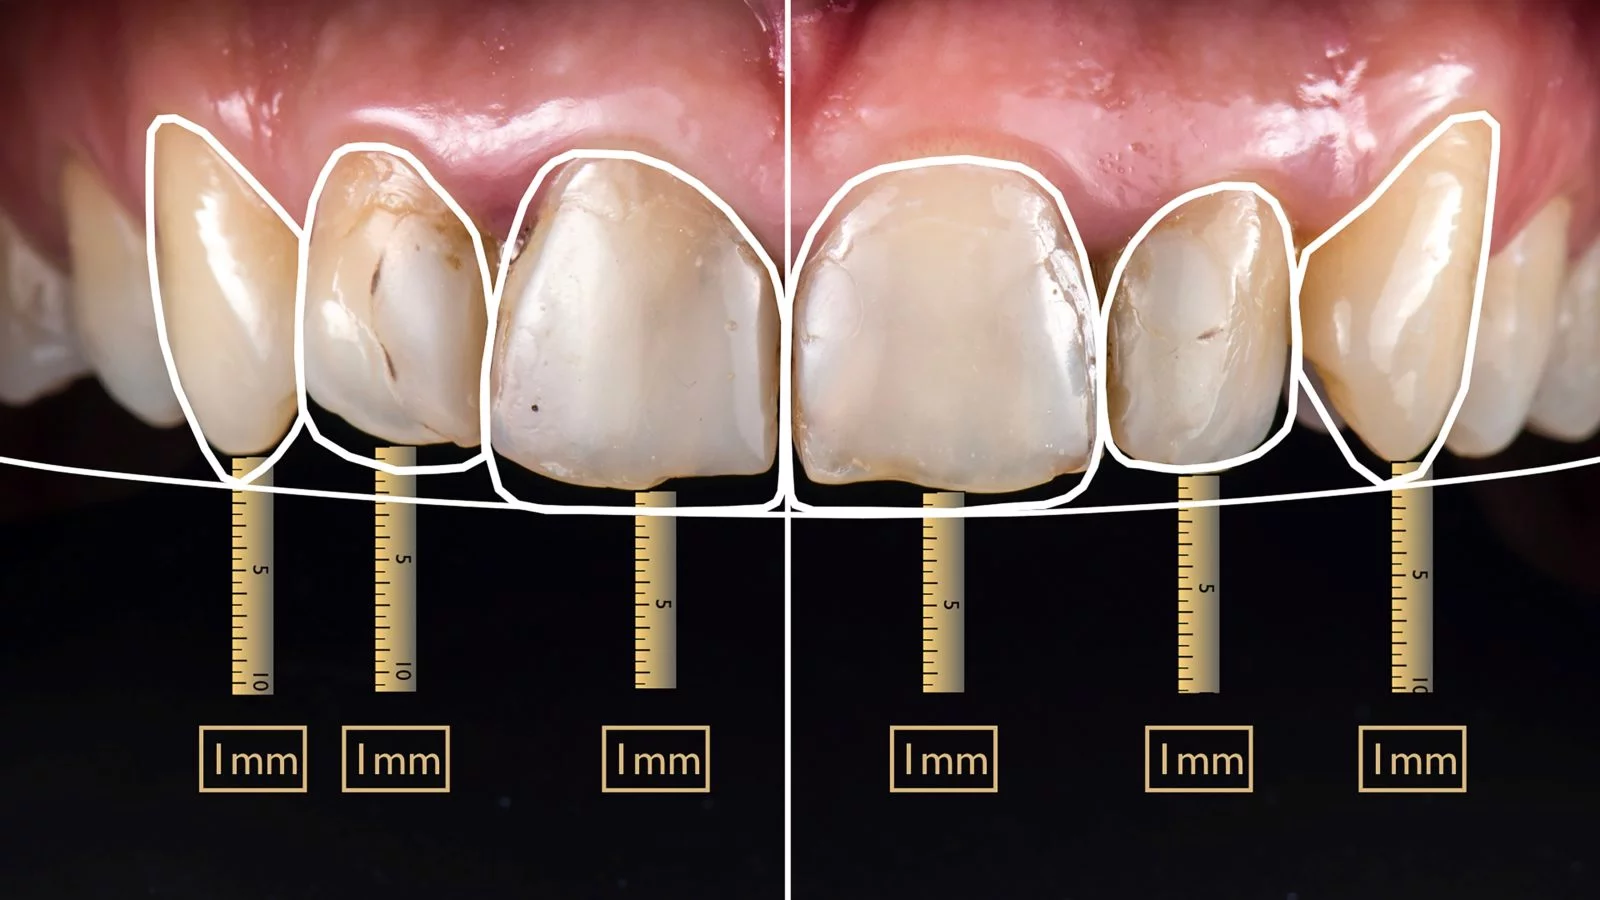

前歯の幅を「中切歯、側切歯、犬歯」の比率を「1.6:1:0.6」とすることで、より美しい口元になります。